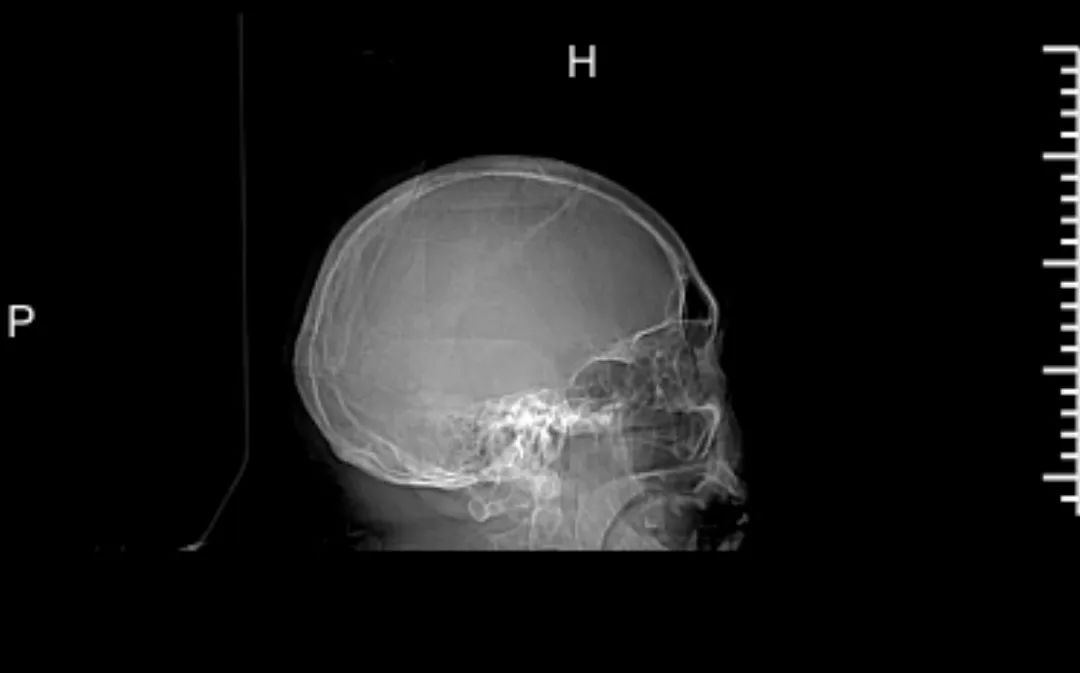

这不,近期我院便收治了一名67岁脑出血患者。凌晨,家属发现患者意识不清,呼之不应,嘴角有少许血症,当时无恶心呕吐,无肢体抽搐,无发热寒战汗出,无气促腹胀等。家属马上呼叫120送我院急诊,入急诊时,患者意识不清,刺痛足曲,测血压154/103mg,急诊查头颅+肺部+全腹部CT提示:1、左侧基底节出血,少许蛛血,建议定期复查。2、支气管病变,左下肺感染灶,建议治疗后复查。3、右侧第3前肋陈旧性骨折。4、全腹部平扫未见明显异常。